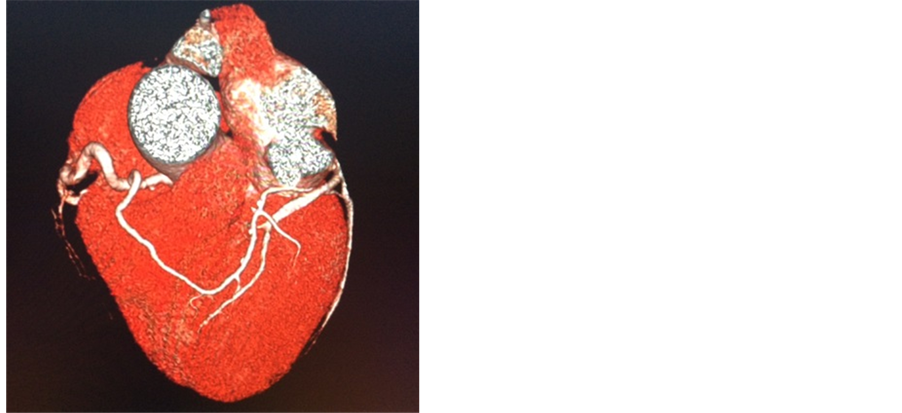

A 57-year-old man (body surface area, 1.9 m2) presented with exertional dyspnea. Transthoracic echocardiography revealed a calcified bicuspid aortic valve (Figure 1) with a mean pressure gradient of 63 mmHg and a calculated aortic valve area of 0.78 cm2, consistent with severe stenosis. Left ventricular ejection fraction was preserved at 65%. Preoperative coronary angiography demonstrated a single coronary artery above the right coronary cusp. The left coronary artery originated from the proximal portion of the right coronary artery (Figure 2). Three-dimensional computed tomography angiography demonstrated that the left coronary artery traveled anteriorly from its anomalous origin and across the conus arteriosus before anatomically correct bifurcation into left anterior descending and left circumflex vessels (Figure 3). No associated coronary artery disease was observed. Aortic valve replacement was performed via full median sternotomy. The ascending aorta was cannulated, and venous cannulation was performed through the right atrium. The patient’s core body temperature was slowly decreased to 35.5˚C. Myocardial protection was achieved using a combination of antegrade and retrograde cold bloodcardioplegia. The annulus sized to a 23 valve. The right coronary artery ostium was identified above the right coronary cusp via preoperative three-dimensional computed tomography angiography. The right coronary artery ostium was only 7 mmabove the annulus. We modified the procedure because of this proximity and the associated risk of coronary ostium occlusion if we set the valve supra-annularly. The 21-mm Aortic Magna Ease Valve (Edwards, Inc., Irvine, CA) was placed intra-annularly using everting sutures. The patient recovered uneventfully and was discharged home on postoperative day 7. He provided written informed consent for publication of this case report and all accompanying images.

Figure 3. Single coronary 3D CT angiography.

In this case, a single anomalous coronary artery was classified as Group II, Type R II-A because the left anterior descending artery arose from the right coronary artery and traversed the anterior surface to reach the inter ventricular groove [3] . As our patient had the anomalous coronary artery and bicuspid aortic valve, many individuals with a single coronary artery have additional congenital cardiac anomalies. Ogden and colleagues reported that 56/142 patients with a single coronary artery had other congenital cardiac anomalies; seven also had a bicuspid aortic valve [4] .